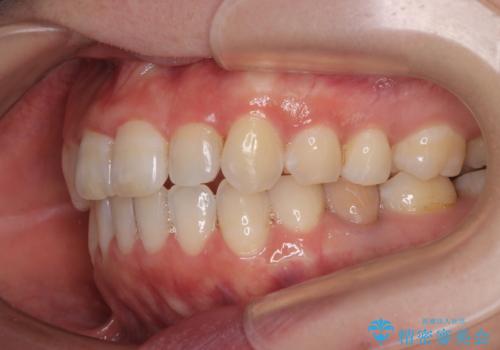

【モニター】飛び出した上顎前歯 補助装置を併用したインビザライン矯正治療

- 上下前歯が非接触となり、前方に突出していることを気にして来院された患者様です。

上下の前後差が大きいため、インビザライン単独での上顎歯列移動は困難と判断し、補助装置により上顎歯列を後方移動させ、その後インビザラインにて仕上げていくこととしました。

補助装置なしでも改善できる可能性はありましたが、補助装置で確実性を上げ、短期間できっちりと仕上げることができました。